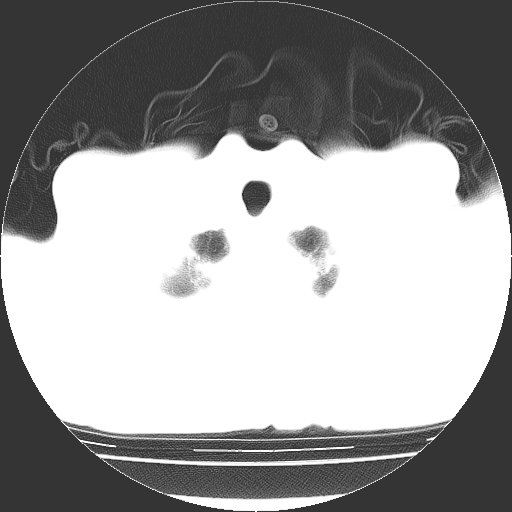

以下是引用hhcckk在2009-1-1 15:38:00的发言:[br]左下肺少许絮状模糊影--考虑感染[br]两肺散在小点状密度增高影--结合病史考虑矽肺?[br]气管壁钙化--可能由于老年退变性引起的